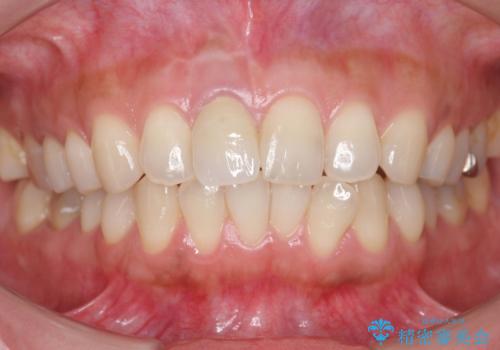

差し歯をもっと自然に 30代女性

- もっと自然にみえるような差し歯にしたいと希望され来院された患者様です。

患者様の天然歯はグラデーションがあり切縁(歯冠の先端)はやや透けていて透明感があるのに対し、前歯(右上1)の差し歯はやや黄色く不透明で単調な色味でした。

前歯のクラウンは一度修正し、患者様の理想とする色味や形態を追求しました。

天然歯と見紛うほどの自然な仕上がりに喜んで頂けました。

ジルコニアクラウンの繊細なグラデーション・透明感は熟練した技工士さんの技術の賜物です。

右上1:ジルコニアクラウン スペシャル

右上5:ジルコニアクラウン スタンダード